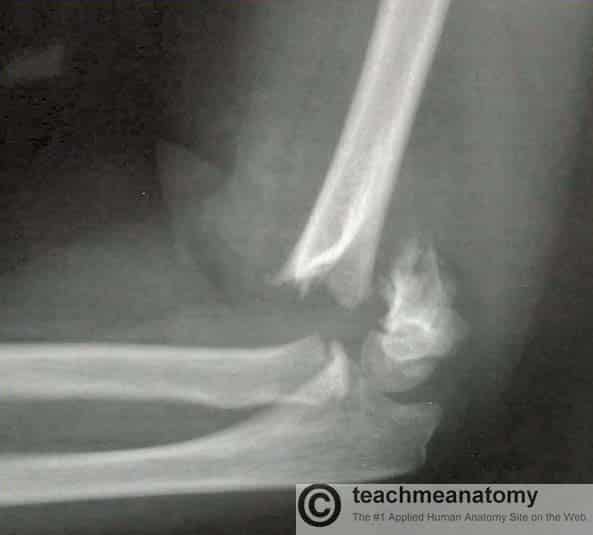

The humerus is a long bone of the upper limb, which extends from the shoulder to the elbow. The proximal aspect of the humerus articulates with the glenoid fossa of the scapula, forming the glenohumeral joint. Distally, at the elbow joint, the humerus articulates with the head of the radius and trochlear notch of the ulna. In this article, we shall look at the anatomy of the humerus – its bony landmarks and clinical correlations. By Anatomography [CC BY-SA 2.1 jp], via Wikimedia Commons Fig 1The anatomical position of the humerus Pro Feature - 3D Model You've Discovered a Pro Feature Access our 3D Model Library Explore, cut, dissect, annotate and manipulate our 3D models to visualise anatomy in a dynamic, interactive way. Learn More Proximal Landmarks The proximal humerus is marked by a head, anatomical neck, surgical neck, greater and lesser tuberosity and intertubercular sulcus. The upper end of the humerus consists of the head. This faces medially, upwards and backwards and is separated from the greater and lesser tuberosities by the anatomical neck. The greater tuberosity is located laterally on the humerus and has anterior and posterior surfaces. It serves as an attachment site for three of the rotator cuff muscles – supraspinatus, infraspinatus and teres minor – they attach to superior, middle and inferior facets (respectively) on the greater tuberosity. The lesser tuberosity is much smaller, and more medially located on the bone. It only has an anterior surface. It provides attachment for the last rotator cuff muscle – the subscapularis. Separating the two tuberosities is a deep groove, known as the intertubercular sulcus. The tendon of the long head of the biceps brachii emerges from the shoulder joint and runs through this groove. The edges of the intertubercular sulcus are known as lips. Pectoralis major, teres major and latissimus dorsi insert on the lips of the intertubercular sulcus. This can be remembered with the mnemonic “a lady between two majors”, with latissimus dorsi attaching between teres major on the medial lip and pectoralis major laterally. The surgical neck extends from just distal to the tuberosities to the shaft of the humerus. The axillary nerve and circumflex humeral vessels lie against the bone here. By TeachMeSeries Ltd (2025) Fig 2The proximal aspect of the humerus. Note the greater and lesser tuberosities as a site of attachment for muscles. Clinical Relevance Surgical Neck Fracture The surgical neck of the humerus is a frequent site of fracture – usually by a direct blow to the area, or falling on an outstretched hand. The key neurovascular structures at risk here are the axillary nerve and posterior circumflex artery. Axillary nerve damage will result in paralysis to the deltoid and teres minor muscles. The patient will have difficulty performing abduction of the affected limb. The nerve also innervates the skin over the lower deltoid (regimental badge area), and therefore sensation in this region may be impaired. Shaft The shaft of the humerus is the site of attachment for various muscles. Cross section views reveal it to be circular proximally and flattened distally. On the lateral side of the humeral shaft is a roughened surface where the deltoid muscle attaches. This is known is as the deltoid tuberosity. The radial (or spiral) groove is a shallow depression that runs diagonally down the posterior surface of the humerus, parallel to the deltoid tuberosity. The radial nerve and profunda brachii artery lie in this groove. The following muscles attach to the humerus along its shaft: Anteriorly – coracobrachialis, deltoid, brachialis, brachioradialis. Posteriorly – medial and lateral heads of the triceps (the spiral groove demarcates their respective origins). Clinical Relevance Mid-Shaft Fracture A mid-shaft fracture of the humerus risk damage to the radial nerve and profunda brachii artery (as they are tightly bound in the radial groove). The radial nerve innervates the extensors of the wrist. In the event of damage to this nerve (either direct or as a consequence of swelling), the extensors will be paralysed. This results in unopposed flexion of the wrist, known as ‘wrist drop’. There can also be some sensory loss over the dorsal (posterior) surface of the hand, and the proximal ends of the lateral 3 and a half fingers dorsally. By Shoulderdoc.co.uk [CC BY-SA 2.0] Fig 3Wristdrop of the left forearm, as a result of radial nerve palsy. Distal Region The lateral and medial borders of the distal humerus form medial and lateral supraepicondylar ridges. The lateral supraepicondylar ridge is more roughened, providing the site of common origin of the forearm extensor muscles. Immediately distal to the supraepicondylar ridges are extracapsular projections of bone, the lateral and medial epicondyles. Both can be palpated at the elbow. The medial is the larger of the two and extends more distally. The ulnar nerve passes in a groove on the posterior aspect of the medial epicondyle where it is palpable. Distally, the trochlea is located medially, and extends onto the posterior aspect of the bone. Lateral to the trochlea is the capitulum, which articulates with the radius. Also located on the distal portion of the humerus are three depressions, known as the coronoid, radial and olecranon fossae. They accommodate the forearm bones during flexion or extension at the elbow. By TeachMeSeries Ltd (2025) Fig 4Bony landmarks of the distal humerus. It articulates with the radius and ulna to form the elbow joint. Articulations The proximal region of the humerus articulates with the glenoid fossa of the scapula to form the glenohumeral joint (shoulder joint). Distally, at the elbow joint, the capitulum of the humerus articulates with the head of the radius and the trochlea of the humerus articulates with the trochlear notch of the ulna. Clinical Relevance Supracondylar Fracture A supracondylar fracture is a fracture of the distal humerus just above the elbow joint. The fracture is typically transverse or oblique, and the most common mechanism of injury is falling on an outstretched hand. It is more common in children than adults. In this type of injury, the brachial artery can be damaged; either directly, or via swelling following the trauma. The resulting ischaemia can cause Volkmann’s ischaemic contracture – uncontrolled flexion of the hand – as flexor muscles become fibrotic and short. There also can be damage to the anterior interosseous nerve (branch of the median nerve), ulnar nerve or radial nerve. The anterior interosseous nerve can be tested by asking the patient to make an ‘okay’ sign, testing for weakness of flexor pollicis longus. The Gartland classification is used for these fractures: Type 1 is minimally displaced Type 2 is displaced with but with an intact posterior cortex Type 3 is completely off-ended. Type 1 can usually be managed conservatively with an above elbow cast whereas types 2 and 3 typically require surgical fixation with crossed, bi-cortical k-wires. By TeachMeSeries Ltd (2025) Fig 5A supracondylar fracture of the humerus Do you think you’re ready? Take the quiz below Pro Feature - Quiz The Humerus Question 1 of 3 Submitting... Skip Next Rate question: You scored 0% Skipped: 0/3 1800 More Questions Available Upgrade to TeachMeAnatomy Pro Challenge yourself with over 1800 multiple-choice questions to reinforce learning Learn More Rate This Article